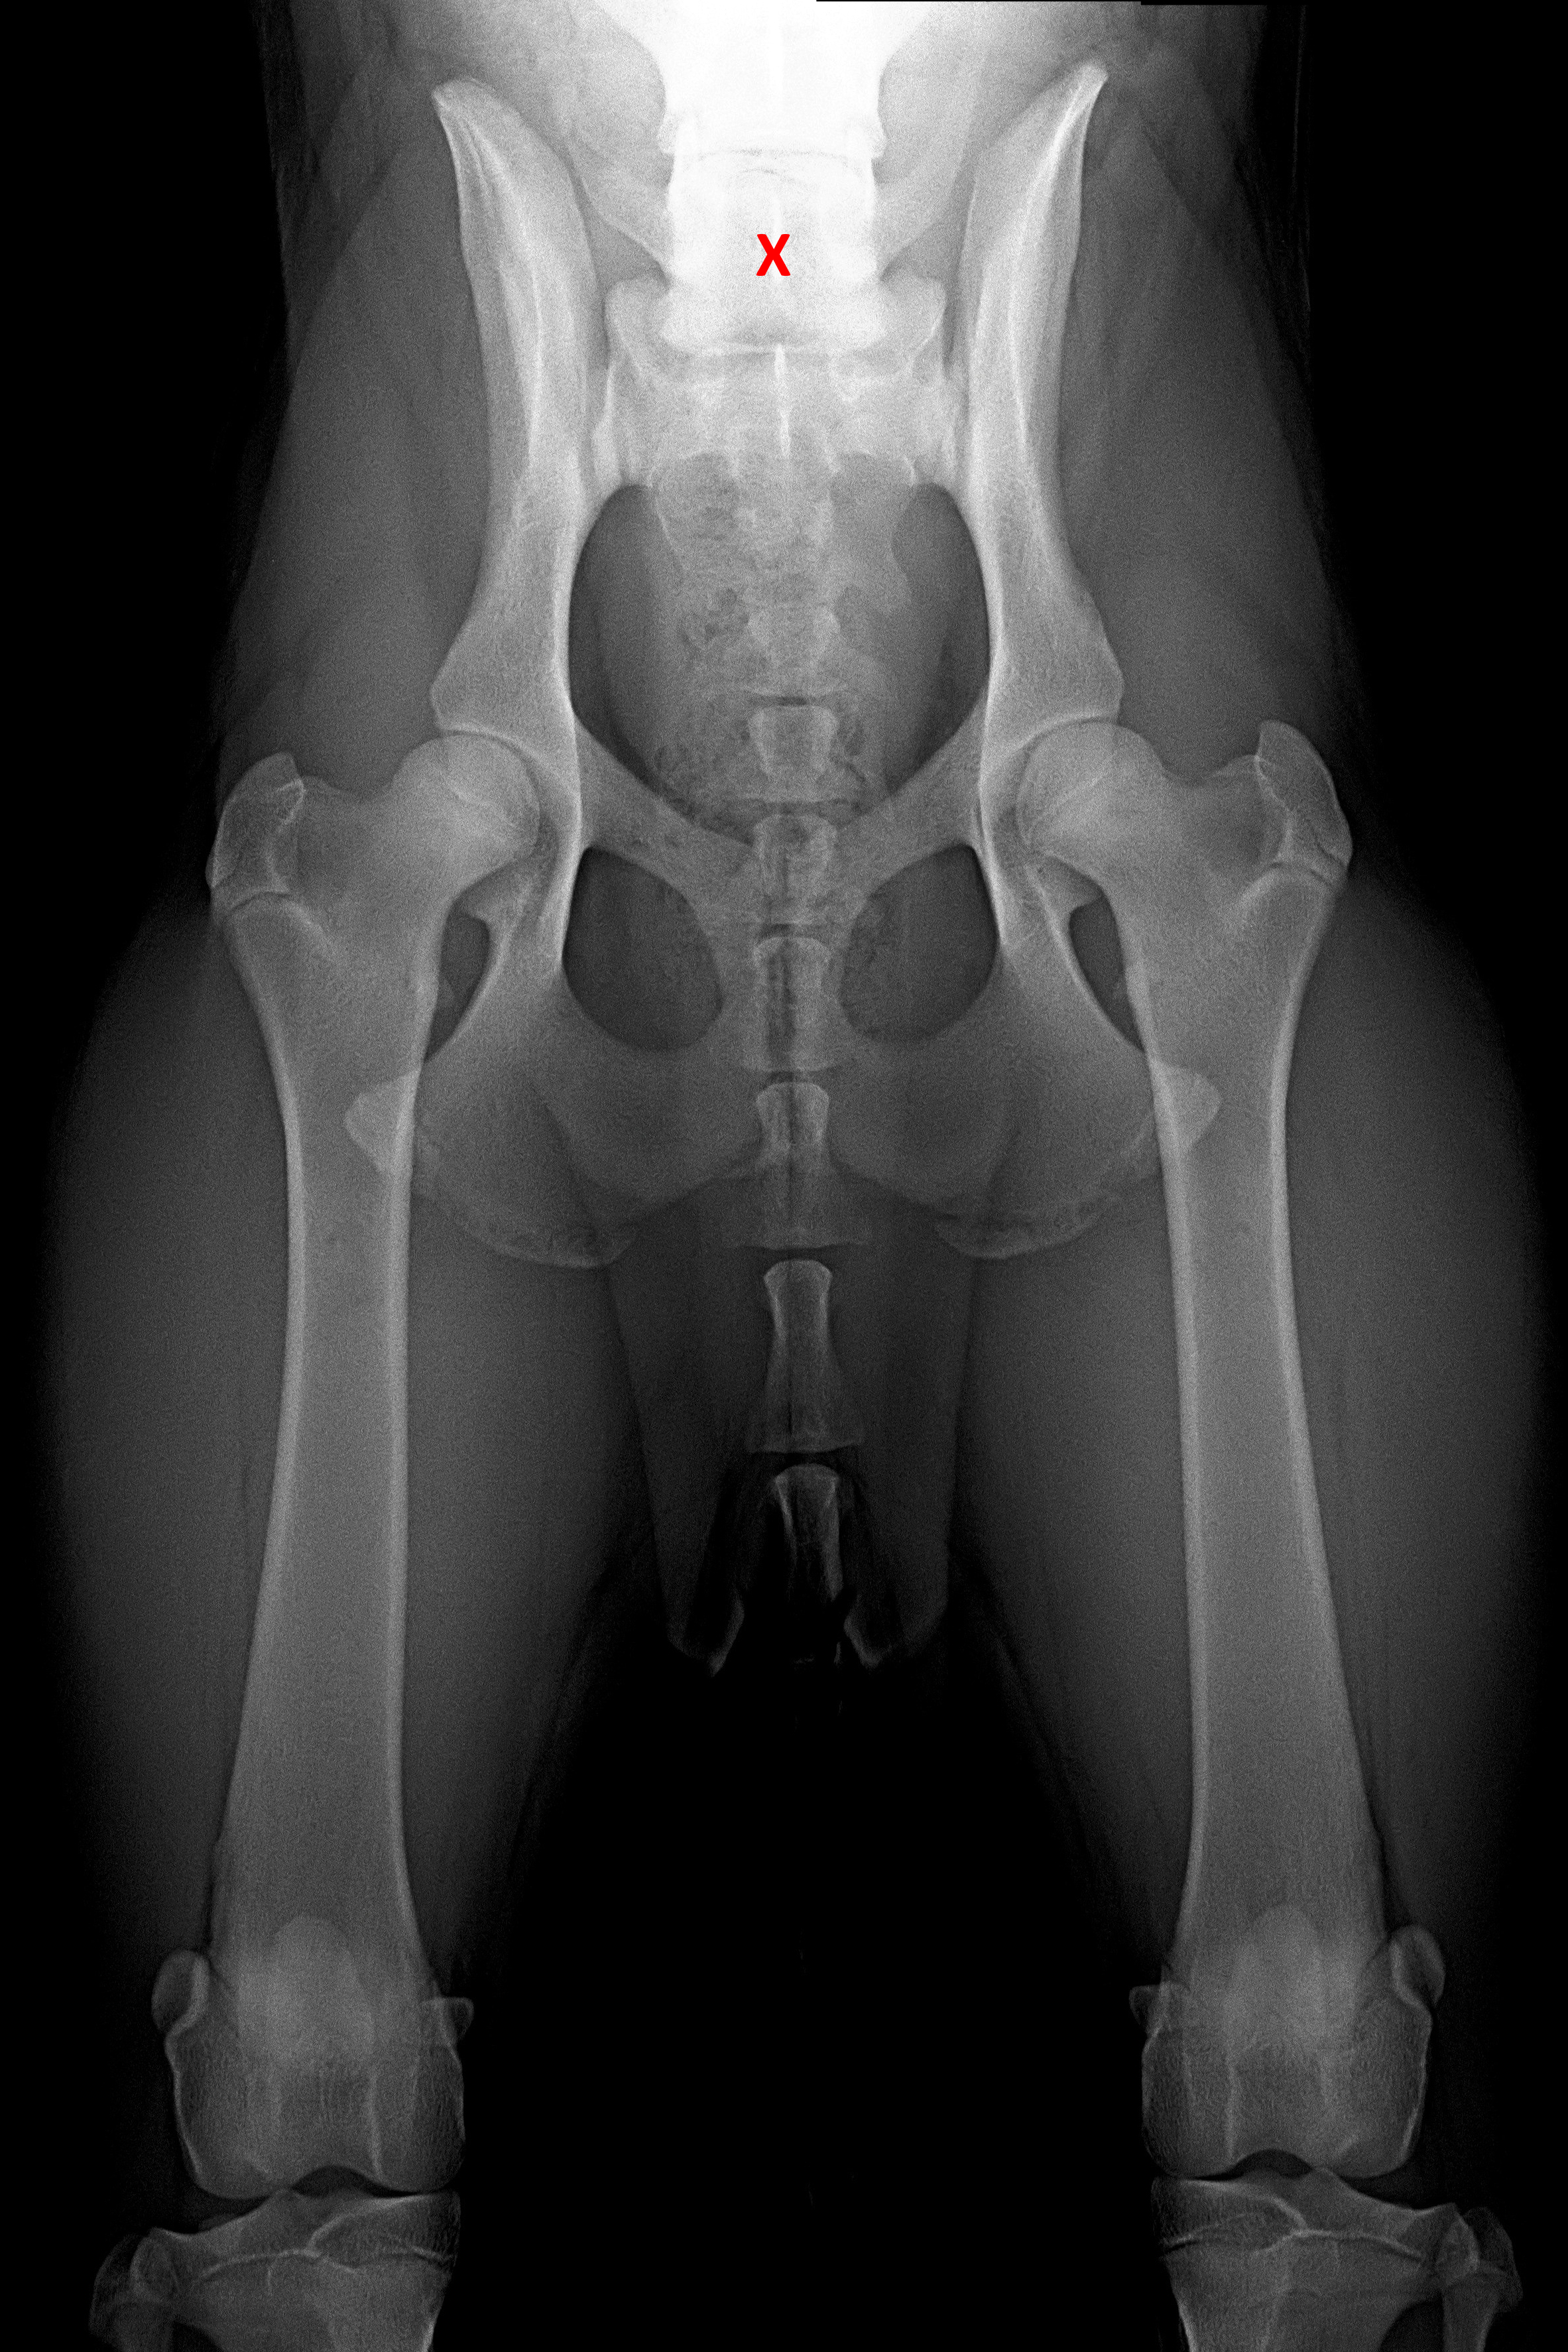

(4) 7 měsíců VD 2

(4) typ 3 po korekci polohy pánve 2